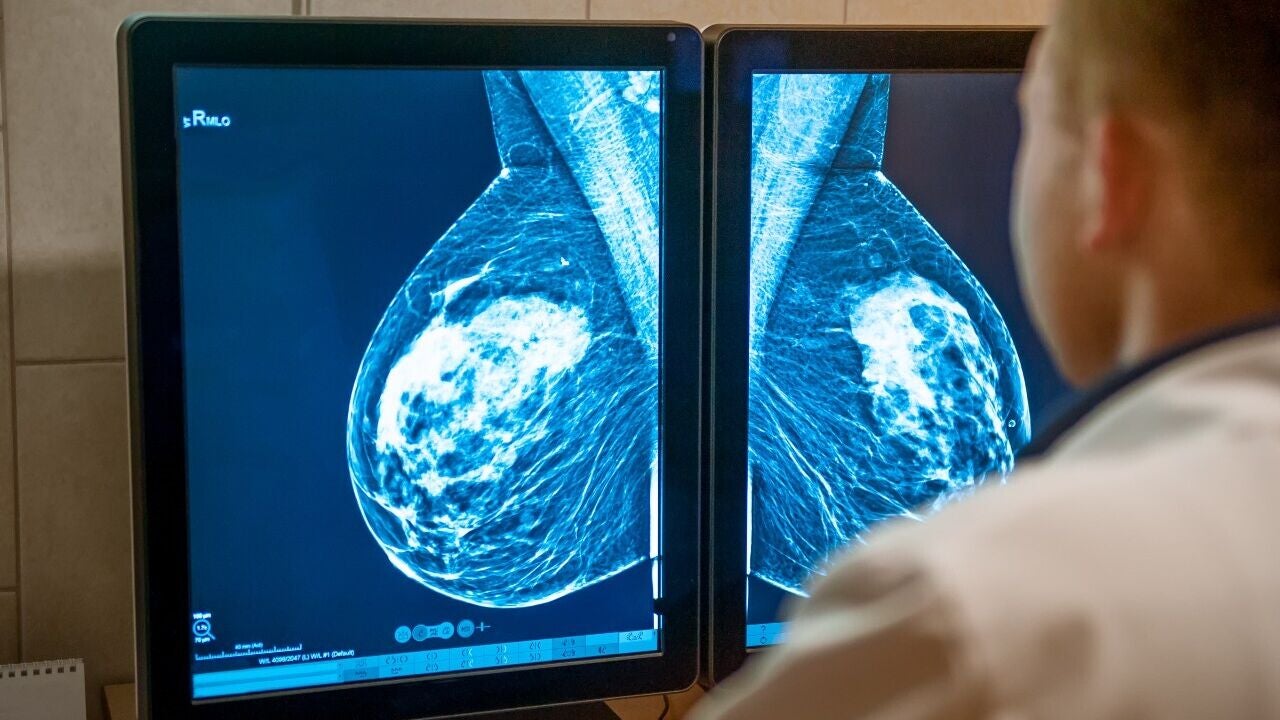

Las operaciones de cáncer de mama han evolucionado hacia intervenciones menos radicales, lo que permite preservar una mayor calidad de vida. Hoy, la cirugía conservadora es el abordaje quirúrgico predominante para las pacientes diagnosticadas en un estadio inicial. A diferencia de la mastectomía tradicional, no solo implica la resección completa del tumor, sino también la conservación de una cantidad adecuada de tejido sano para mantener la integridad estética.

Sin embargo, al dejar más tejido sano también aumenta la posibilidad de que queden algunas células tumorales tras la cirugía, lo que eleva el riesgo de recaída. Por lo tanto, es fundamental que los cirujanos visualicen los márgenes de tejido que rodean al tumor, para asegurarse de que están libres de cáncer.

Un nuevo estudio, publicado esta semana en la revista Science Traslational Medicine, muestra una sonda de imagen capaz de detectar con exactitud los tumores antes de la operación, lo que permite extirparlos salvando al máximo el tejido mamario que no está afectado.